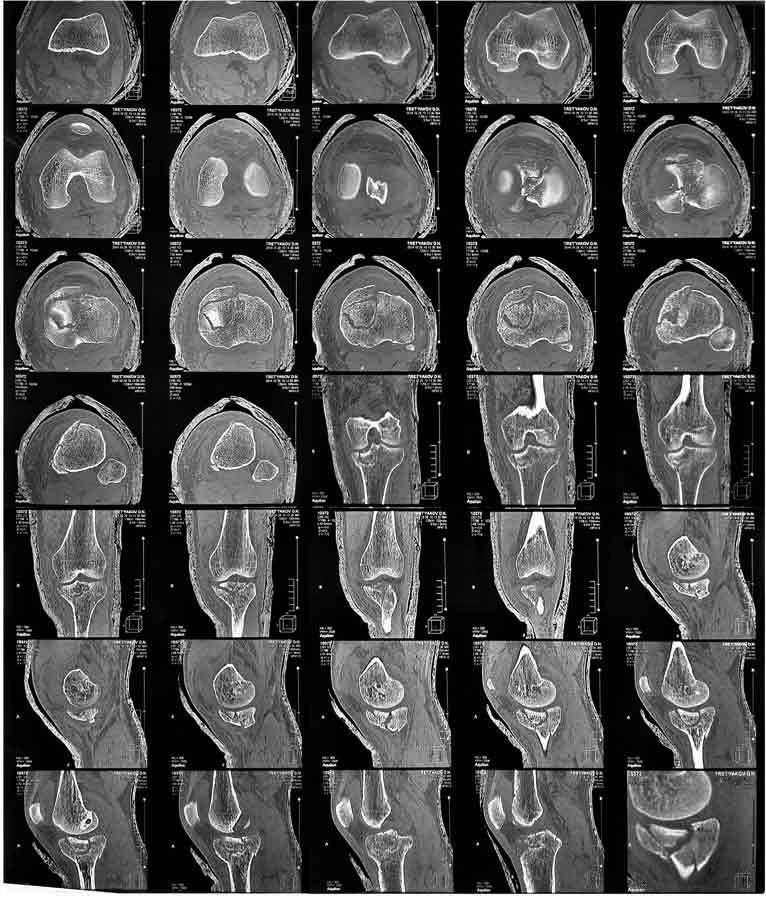

Мужчина, 36 лет, импрессионный перелом медиального (внутреннего) мыщелка ББК левой ноги.

С его слов обстоятельства травмы: Прыгнул с высоты около 3м и при приземлении подвернул ногу.

Прилагаю снимки ренген + КТ Подскажите пожалуйста, какой фиксатор подойдет для данного перелома.